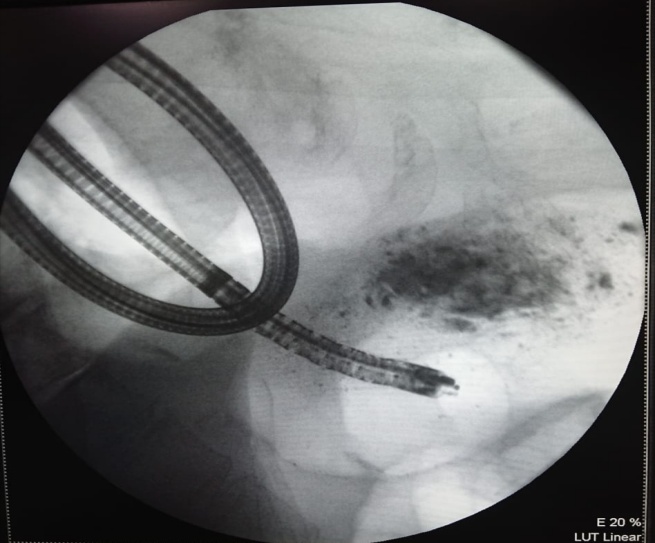

В течение сут на фоне инфузионной, спазмолитической терапии существенной положительной динамики не отмечалось, продолжалась рвота до 8 раз в сут, сопровождающаяся выраженным астеническим синдромом, сохранялись боли в левом подреберье и эпигастральной области. В связи с сохраняющейся выраженной рвотой и симптомами дуоденальной непроходимости, а также с целью подготовки пациентки к оперативному лечению под эндоскопическим контролем установлен двухпросветный питательный зонд в просвет желудка и двенадцатиперстной кишки (рис. 6).

Рис. 6. Установка зонда в просвет двенадцатиперстной кишки